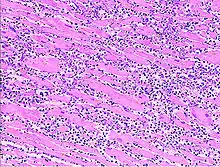

Virale Myokarditis

Ät.: Coxsackie-, ECHO-, Adenoviren, Influenzaviren

Pathogenese: Herzmuskelnekrose durch Virus und T-Zell-vermittelte Immunreaktion.

Mikro: Interstitielles lymphozytäres Infiltrat (kleine blaue Zellen), kaum Nekrosen.

.JPG.webp) Virale Myokarditis bei Patient mit plötzlichem kongestiven Herzversagen, Autopsiepräparat, H&E. |

.JPG.webp) idem. |